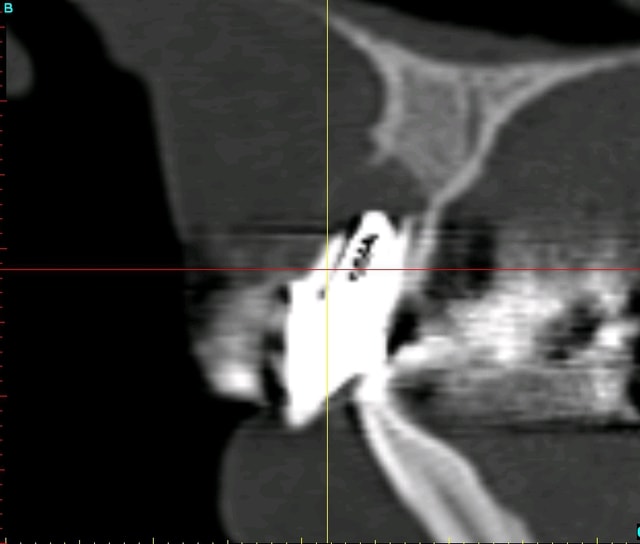

Voilà ce que l'on arrive à faire mais ce fut limite!

Interactive dx8dv8 - Eugenol